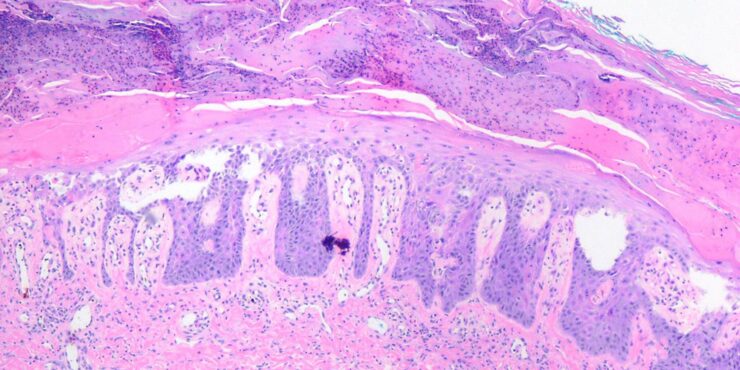

Read Moremetastasis OLYMPUS DIGITAL CAMERA OLYMPUS DIGITAL CAMERA OLYMPUS DIGITAL CAMERA OLYMPUS DIGITAL CAMERA OLYMPUS DIGITAL CAMERA OLYMPUS DIGITAL CAMERA